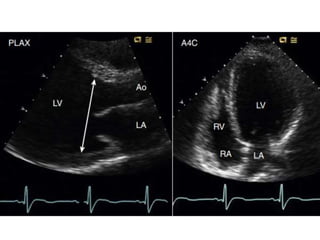

Aortic Valve Prolapse Echo